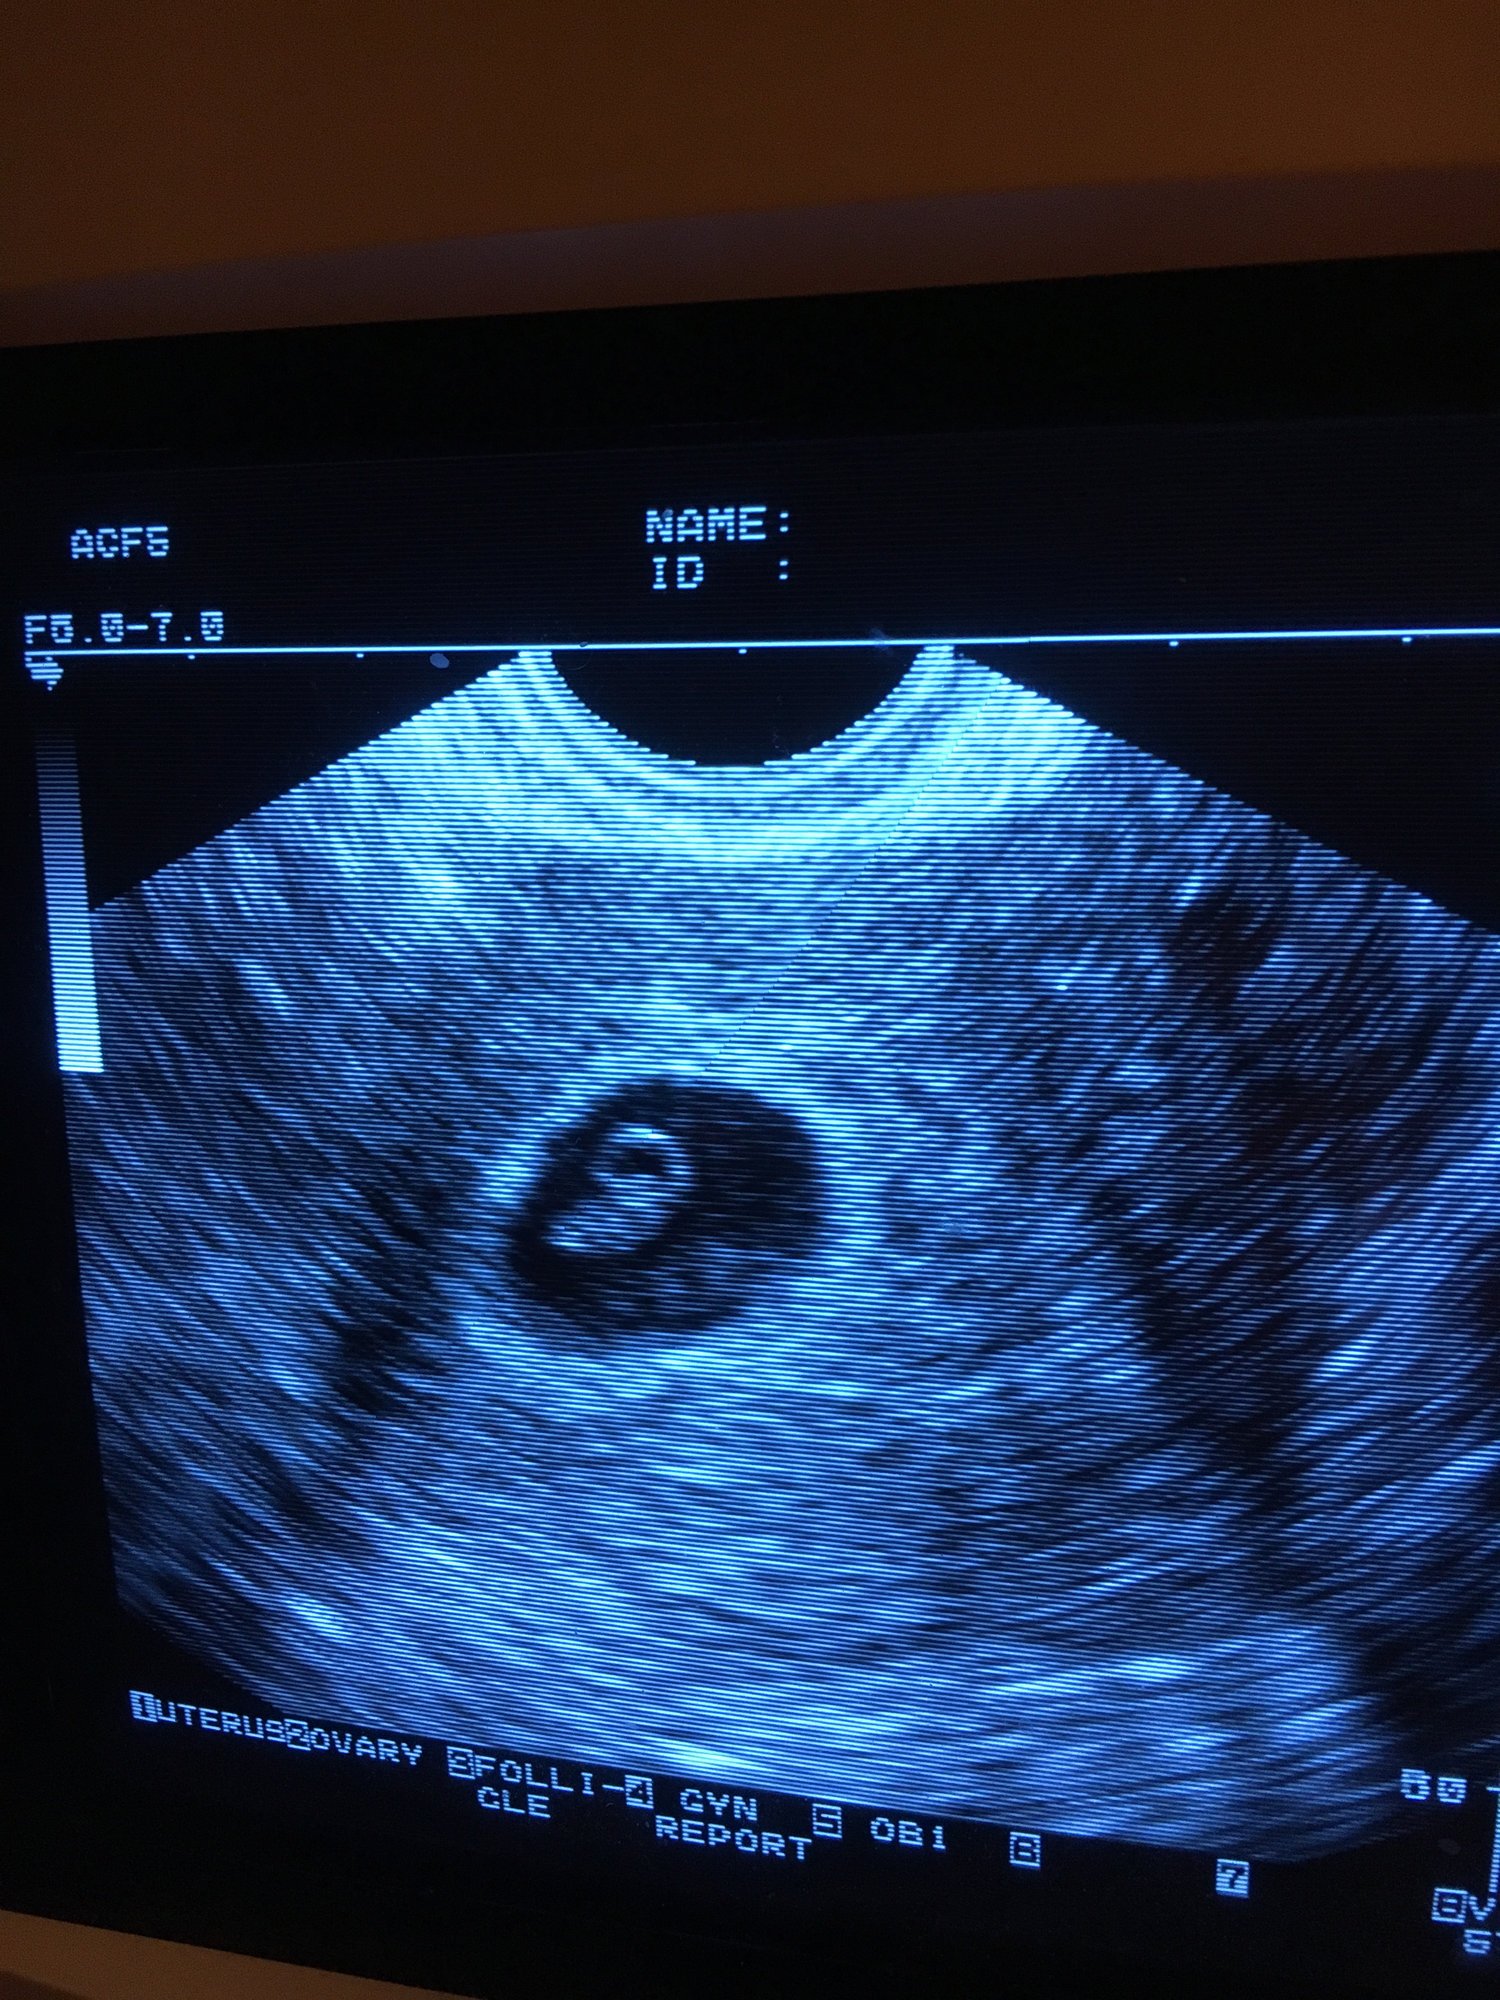

If you see the two little dots in the black of my uterus, you'll realize there's twins in there! As of right now though, they're looking to be monoamniotic-monochorionic twins. This means they share a placenta and an amniotic sac, or they likely will if one of the twins doesn't get reabsorbed. However, since they both had their own yolk right now, it's poooooooosible (but not likely) that they'll each develop their own amniotic sacs. The result is either going to be that one of the twins will be lost or I will have a very high risk mo-mo pregnancy.

@expandcontract Definitely freaking out. Hubs and I want both these babies but right now there's a lot of wiggle room for things to go very wrong. The doctor heavily implied that by next week's ultrasound one would likely stop growing/start to be reabsorbed. If the babies keep going and she is right about there only being one amniotic sac (which is apparently very rare and there's testimony online of people only seeing the second sac like 18 weeks in) I'm looking at inpatient hospitalization from 23 weeks on.

I'm trying not to get my hopes up but I really want both of these healthy babies.